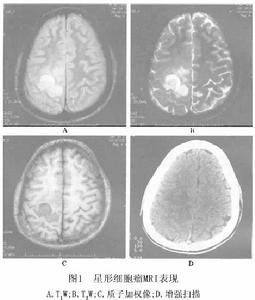

間變性星形細胞瘤CT上呈低密度或不均一低密度與高密度混雜病灶(圖2) 90%腫瘤占位效應明顯,伴有瘤周水腫,20%有囊變,10%可見鈣化。